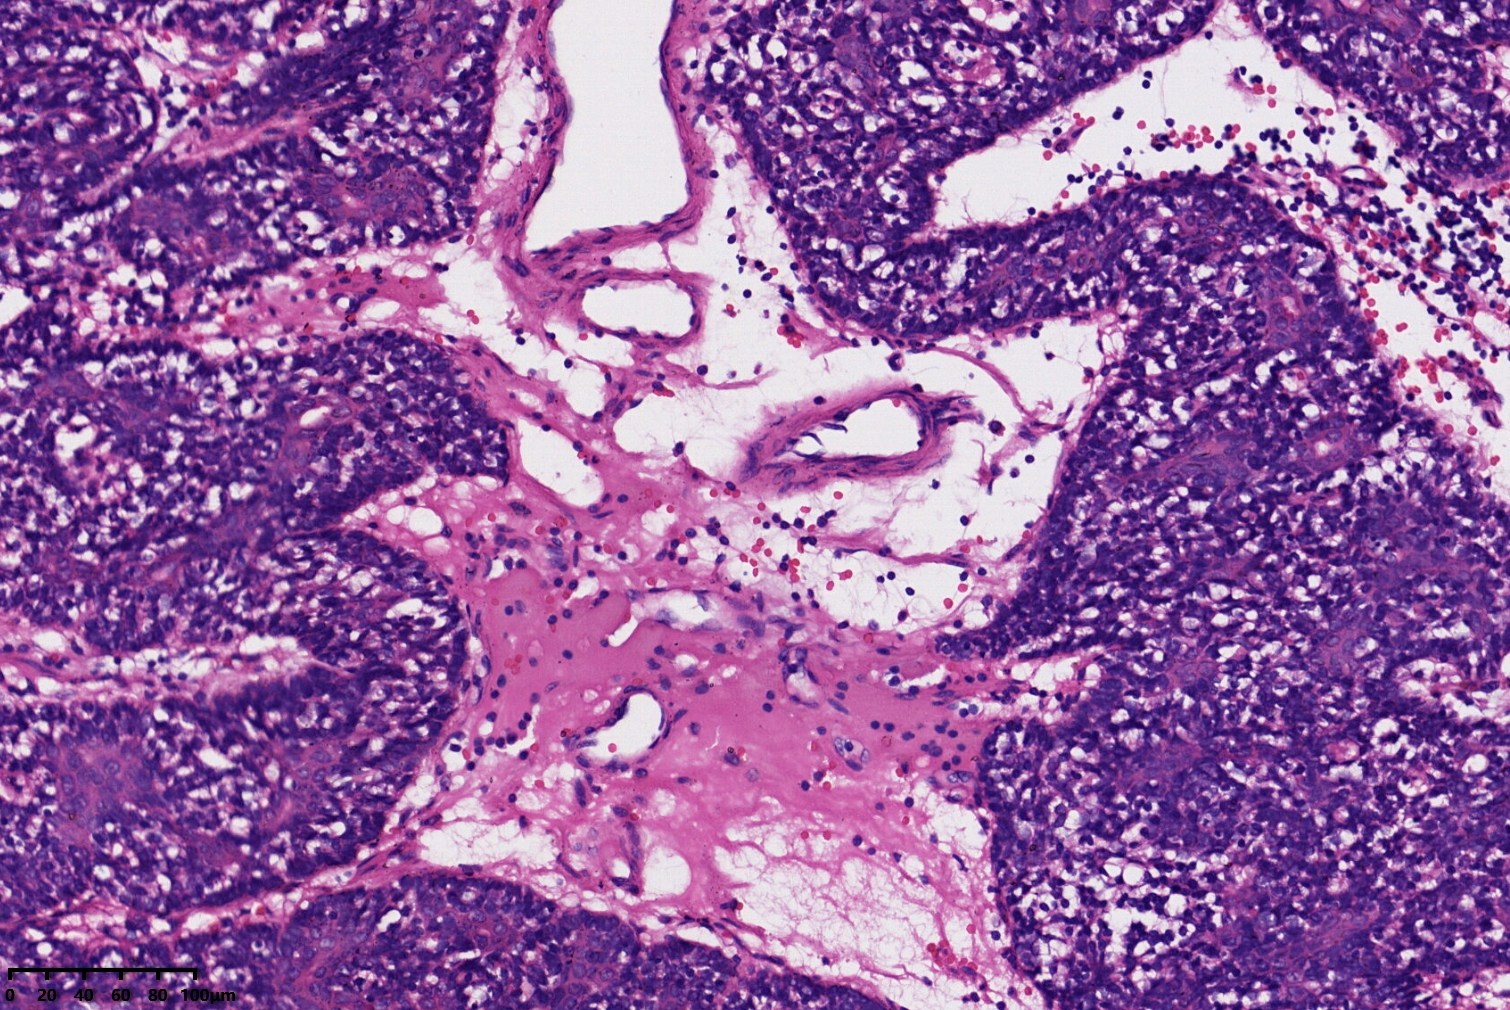

汗腺腺瘤?

背部包块

同意,有的区域像透明细胞汗腺瘤

小汗腺螺旋腺瘤